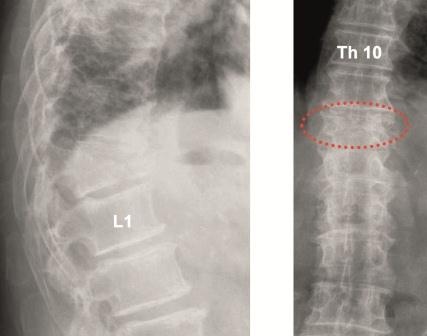

Kyphoplastie: Einfache osteolytische Metastasen können auch bei Hinterkantenbeteiligung üblicherweise bei entsprechenden Vorsichtsmaßnahmen mit der von uns bevorzugten Shieldkyphoplastie versorgt werden (Abb. 1a und b). Die reine Vertebroplastie erscheint uns in diesen Fällen zu riskant. Mit der Shieldkyphoplastie können wir die Osteolyse monopedikulär mit dem gebogenen Bohrer sehr gut adressieren und das Shield-Implantat genau dort platzieren. Perforationen im Shieldimplantat, aus denen der Zement gerichtet nach ventral austreten kann, stellen die Interdigitation mit der umliegenden Spongiosa sicher, wodurch die Stabilität erhöht wird.

Daher erscheint uns die anatomische Bildgebung zur Abklärung dieser Fragestellungen grundsätzlich indiziert. Wir bevorzugen bei allen fraglichen Wirbelsäulenfrakturen ein MRT, mit dem weitere Brüche, die initial nicht zwangsläufig eine Formveränderung aufweisen müssen, identifiziert werden können. Bei Kontraindikationen für eine MRT kombinieren wir die Sintigraphie mit einer CT. Zudem halten wir bei der Kyphoplastie eines vermeintlich osteoporotischen Wirbelbruchs wann immer möglich eine Gelegenheitsbiopsie für sinnvoll. In der Regel reichen Knochenfragmente aus dem Wirbelkörper, die am Bohrer haften oder eine Stanzbiopsie über den Arbeitskanal zur histopathologischen Aufarbeitung aus. Für den Patienten entsteht so keine zusätzliche Gefährdung. Bei diesem Vorgehen werden hin und wieder unerwartet insbesondere ein Plasmozytom oder eine Mammakarzinommetastase identifiziert. Häufig kann jedoch schon anhand der konventionellen bildgebenden Diagnostik auf eine Metastase geschlossen werden.